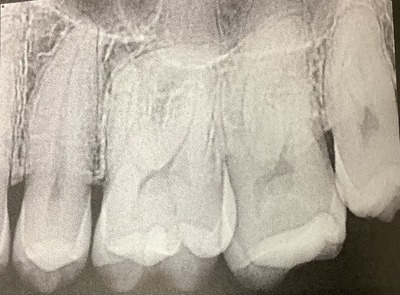

根っこの神経への入り口が見つかるように、神経の部屋の床部分を出します。

残っている歯を評価するためにも、前の治療や虫歯は全部取り除きます。

最近は出来るだけ小さく削るのが注目されています。

出来るだけ多くの象牙質を残すためです。

神経の部屋の天井部分を多く残すことで、折れにくくなります。